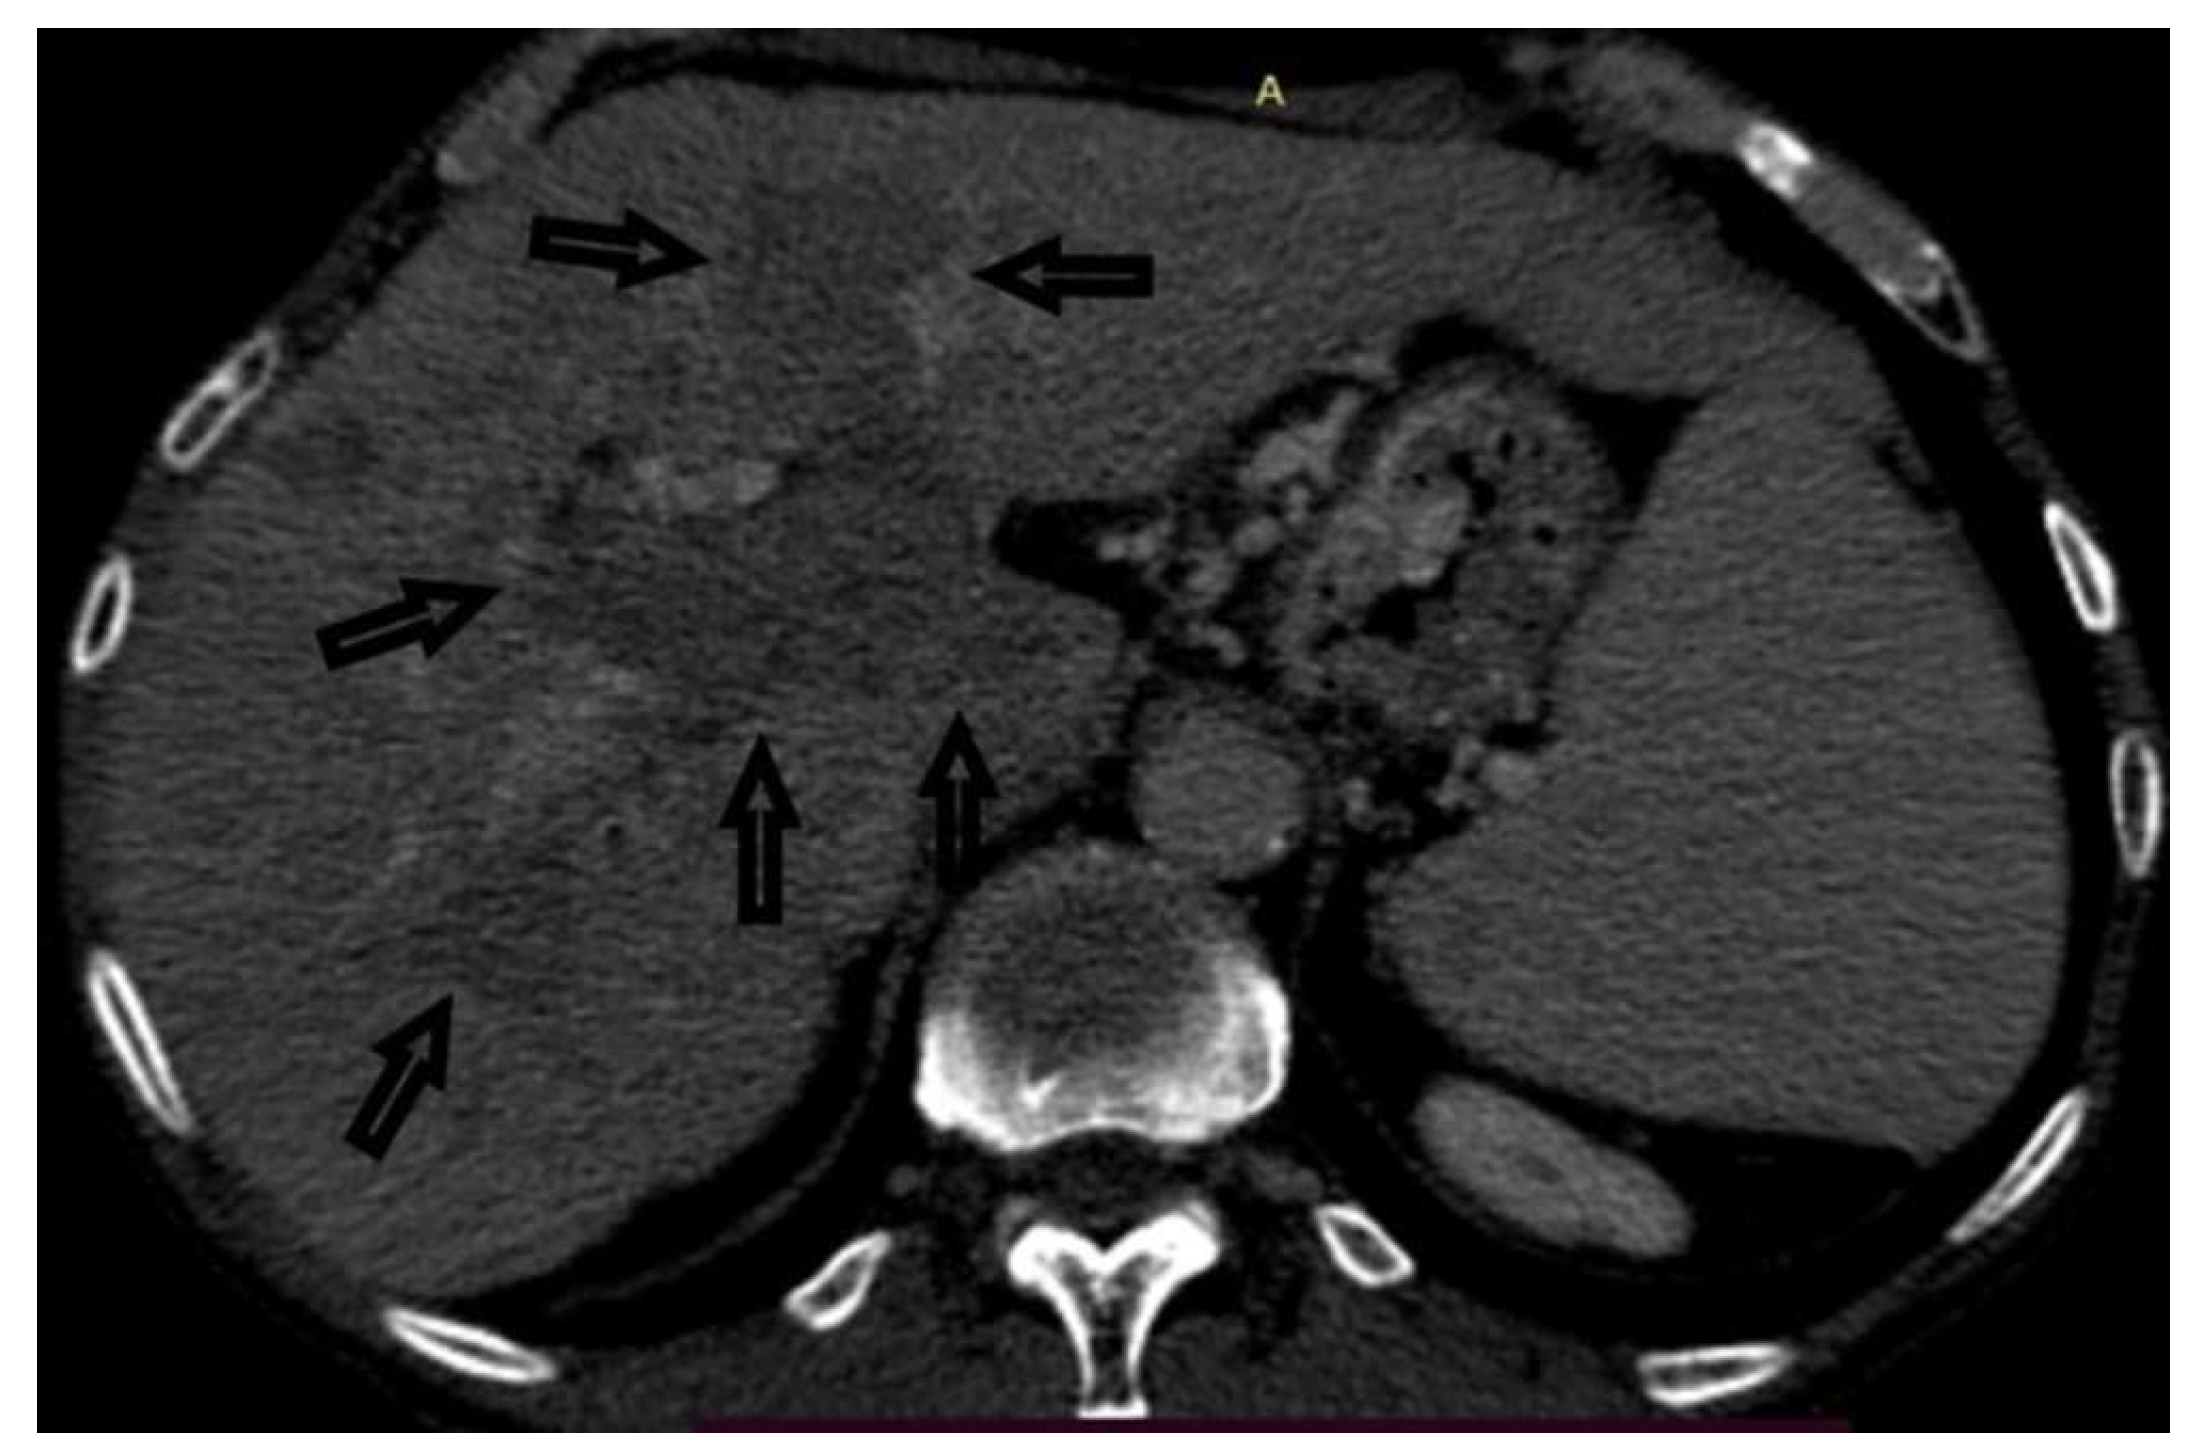

Figure 1. MDCT of the abdomen, portal phase: an altered morphology of the right lobe of the liver with thrombosis of the main stem and the right branch of the portal vein, which are hypovascular, is observed - indicated by arrows. Ascites. Smaller retroperitoneal lymph nodes.

Case 1: A 72-year-old female, hospitalized for diarrhea and occasional abdominal pain for the last two months, followed by a loss of appetite and subsequent weight loss. PVT was detected ultrasonographically and in an enlarged, heterogeneous liver without a well-defined tumor mass. Abdominal MDCT has shown changes in the right liver lobe morphology, signs of PVT, ascites, and retroperitoneal lymphadenopathy (Figure 1). An MRI examination could not be performed due to the presence of the patient’s implants. AFP levels were significantly increased. A CNB was performed via the anterior abdominal wall, obtaining three samples from the right liver lobe, proximally to PV, and two pieces from the portal vein thrombus (Figure 2 and Figure 3). Pathohistological findings confirmed a poorly differentiated HCC in PVT samples. The other three samples did not provide any signs suggestive of HCC. Following a successful diagnosis, the oncological treatment could begin.